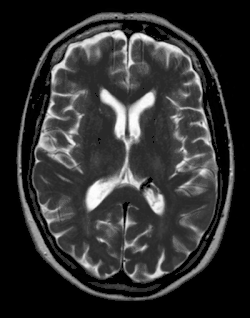

AVM des Gehirns in der Magnetresonanztomographie

• Arteriovenöse Malformationen (AV-Malformation, AVM): dies sind direkte Gefäßverbindungen zwischen Arterien und Venen ohne Kapillarbett. Das arterielle (sauerstoffreiche) Blut kommt aus einer Arterie und fließt direkt in eine Vene ab, ohne dass der darin enthaltene Sauerstoff von Gewebe verbraucht wird. Bei entsprechender Größe der AVM kann es zu einem Übertritt eines nicht unerheblichen Blutvolumens kommen, was als Steal-Syndrom klinisch relevant werden kann.